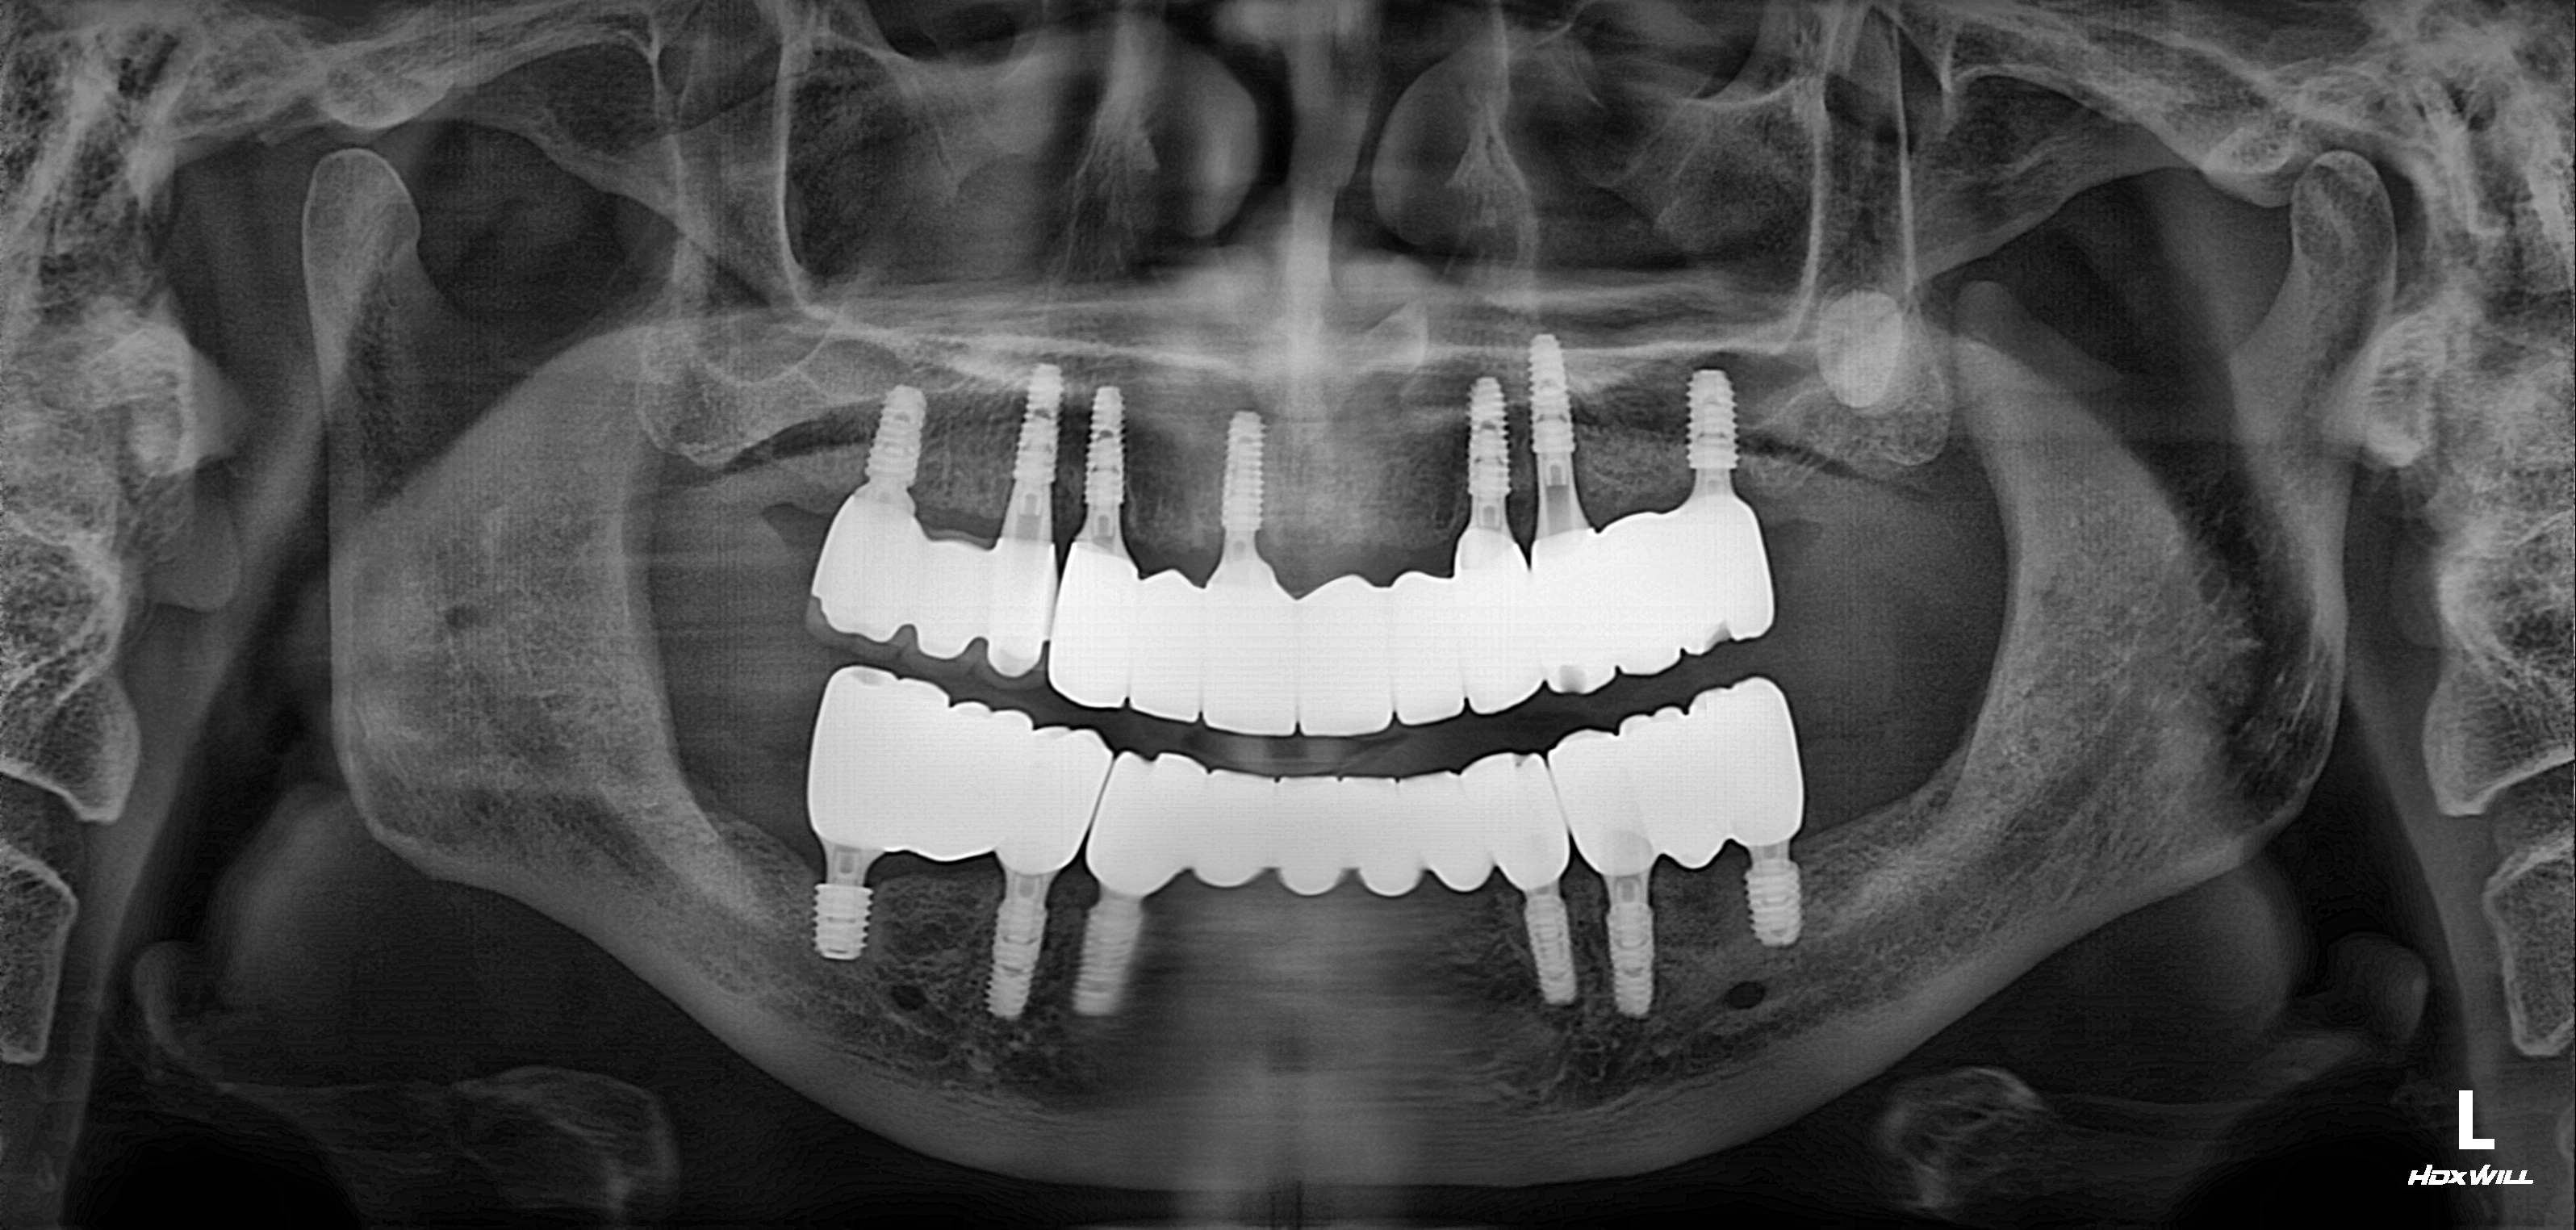

전악 임플란트 식립사례

전후사진

수술 전

수술 후